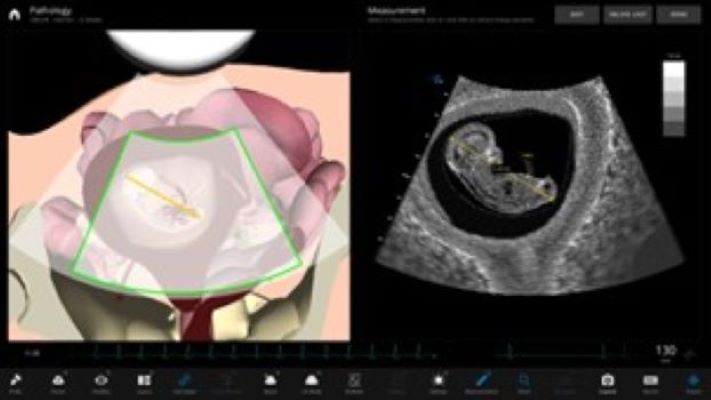

Ecografía intraparto (1h) - Obesidad y embarazo (1h)

- Utilizar la ecografía como un método de diagnóstico para mejorar la sensibilidad diagnóstica de la exploración física

- Mejorar la sensibilidad diagnóstica del tacto vaginal

- Principios de la ecografía intraparto

- Indicaciones y limitaciones de la técnica

Ecografía obstétrica intraparto para obstetras

Estos talleres se realizan con la colaboración de la fundación imaterna.

Destinatarios: Obstetras

Duración: 2h

Plazas: 15 por edición

- CONTENIDOS

- Principios de ecografía intraparto

- Ecografía y dilatación cervical

- Cortes básicos de ecografía intraparto

- Distancia Cabeza periné

- Angulo de progresión

Pruebas invasivas ecoguiadas en obstetricia (amniocentesis + biopsia corial)

Se trata de adquirir conocimientos teóricos con la información previa y un taller de entrenamiento en punción guiada por ecografía en un simulador para practicar la biopsia corial tanto abdominal como vaginal y la amniocentesis.

Plazas: 10 por edición

- Técnica de la amniocentesis

- Técnica de biopsia corial transabdominal

- Técnicas de la biopsia corial transcervical